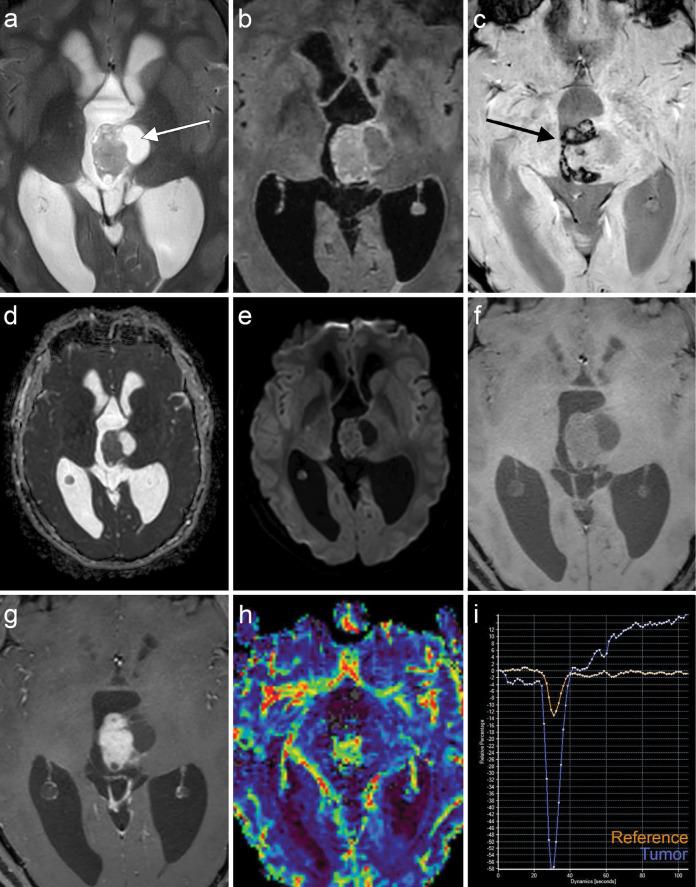

并且()基因融合的中枢神经系统(CNS)肿瘤越来越被认为是一种潜在的独特实体,报告的病例有限。这些肿瘤的影像学特征尚未完全明确。在本研究中,我们对一名24岁男性病例进行了详细的放射学描述,并进行文献综述以确定常见的影像学特征。总共评估了包括我们自己病例在内的7例病例。组织病理学诊断包括2例室管膜瘤、1例婴儿型胶质母细胞瘤、1例成星形细胞瘤、1例神经节胶质瘤和2例未另行分类的胶质瘤。常见的影像学表现包括明显的对比增强、瘤内囊肿、脑室位置或扩展导致脑积水以及边界清晰。其他常见特征包括钙化和出血灶。总之,尽管基因融合的中枢神经系统肿瘤的组织病理学表现多样,但存在一致的影像学特征。认识到这些特征在诊断过程中可能很有价值,因为放射科医生可能是首先提出诊断的人。

and () gene fusion central nervous system (CNS) tumors are increasingly recognized as a potential distinct entity, with only limited reported cases. The imaging characteristics of these tumors have not been well established. In this study, we provide a detailed radiological description of a case in a 24‑year‑old man and conduct a literature review to identify common imaging features. A total of seven cases, including our own, were evaluated. Histopathological diagnoses included two ependymomas, an infantile glioblastoma, an astroblastoma, a ganglioglioma, and two gliomas not otherwise specified. Common imaging patterns included avid contrast enhancement, intratumoral cysts, intraventricular location or extension leading to hydrocephalus, and sharp delineation. Additional frequently observed features included calcifications and hemorrhagic foci. In conclusion, although the histopathological appearance of gene fusion CNS tumors is diverse, there are consistent imaging features. Recognition of these features can be valuable in the diagnostic process, as radiologists can be the first to suggest the diagnosis.